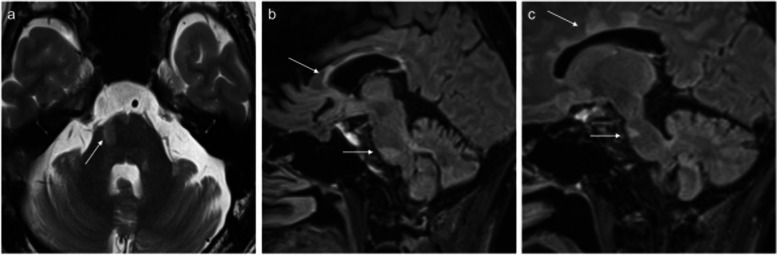

Case presentation: A 49-year-old male with multiple sclerosis exhibited persistent dull pain and paroxysmal electric shock-like pain in his bilateral maxillary molars and mandible. He was diagnosed with trigeminal neuralgia due to multiple sclerosis. Due to severe side effects, it was difficult to achieve adequate pain control with medication alone. By performing low-temperature radiofrequency thermocoagulation and pulsed radiofrequency of the Gasserian ganglion while monitoring masseter muscle contraction, a satisfactory and rapid analgesic effect was obtained without masticatory atonia.